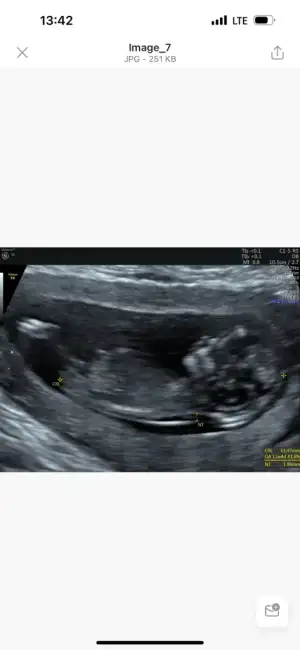

Kızlar ben geldiiim 👋🏻 uzun suredir bugünü bekliyordum ya kontrole gittim bugün. Gece heyecandan yarım yamalak uyudum sürekli rüyamda gördüm falan inanılmaz heyecanlıydım anlayacağınız🤣. 12. Haftalık olduk bugün sata göre ama doktorum 4 gün önden gittiğini söyledi. Bizim minnos inanılmaz hareketliydi, elleri hiç durmuyordu çok zor çektik fotoğraflarını görseniz 🥰 cinsiyet içinde doktorum epey uğraştı ama göstermedi bizimki poposunu kaldırdı durdu hep 🤪 her şey yolundaymış çok şükür 🙏🏻 ikili test zamanımızdı doktorum fetal yapmamızı önerdi ben aslında ikili yapıp ona göre fetal yaptırmayı planlıyordum ama eşim hemen ikna oldu kan verdik haftaya onun da sonucu çıkacak inşallah, cinsiyeti de öğrenmiş olacağız😍

Şimdi benim minnosu ekliyorum T Tali89 ne diyorsun 🥹😍😍